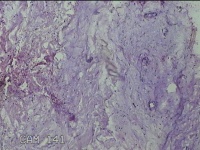

骶尾部包块

性别

男

年龄

37岁

临床诊断

骶良性肿瘤

一般病史

发现骶尾部包块10年余。

标本名称

大体所见

灰白粉红色组织3.5x1.3x1cm一块,表面带梭形皮肤3.5x1.3cm皮下见包块3x1.3cn一个,切开包块呈实性,切面灰白粉红色,质中。

图1